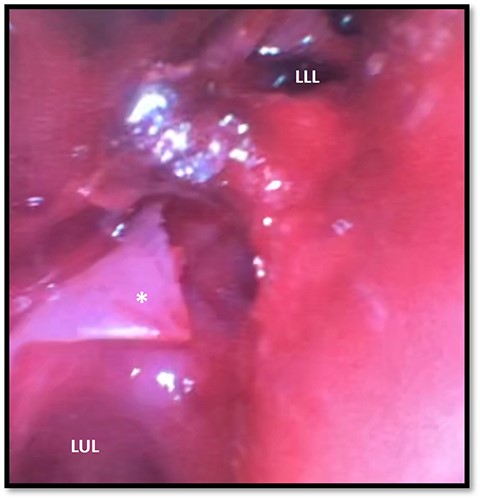

The patient arrived hemodynamically stable and was intubated on single lung ventilation. Repeat bronchoscopy was performed at bedside, which demonstrated a full thickness tear in a spiral fashion spanning the medial to distal left mainstem bronchus with exposure of the pulmonary artery and communication with the mediastinum (Fig. 2). Surgical repair was planned for the following day with thoracic surgery. Prior to definitive repair, an intraoperative bronchoscopy was performed, which noted that the previously seen spiral left bronchial laceration had re-approximated into its original anatomical position, effectively sealing the lumen. Additionally, after double lung ventilation was restarted, there was no appreciable air leak. As such, the operative repair was deferred and the patient was managed with supportive care. A follow-up bronchoscopy was repeated on hospital day (HD) 4, which demonstrated that the left bronchial wall defect had remained closed with overlying intraluminal granulation tissue. Same day CT chest also demonstrated an interval decrease in pneumomediastinum and resolution of pneumothorax (Fig. 3). The patient underwent subsequent external fixation of his right radius and ulnar fractures. He was successfully weaned off of positive pressure ventilation on HD 11 and his chest tubes were subsequently removed. He was deemed to be medically stable for discharge on HD 15 and underwent outpatient stenting of his acquired bronchial stenosis.

Bronchoscopy demonstrating left main stem bronchial tear (*) just proximal to the take between the LUL and LLL bronchi division; a hematoma can be seen obstructing the full view of the LLL; LUL, left upper lobe; LLL, left lower lobe.